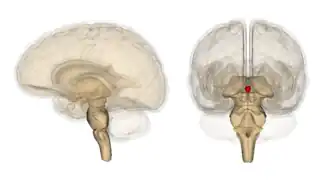

The pineal gland (also known as the pineal body[1] or epiphysis cerebri) is a small endocrine gland in the brain of most vertebrates. It produces melatonin, a serotonin-derived hormone, which modulates sleep patterns following the diurnal cycles.[2] The shape of the gland resembles a pine cone, which gives it its name.[3] The pineal gland is located in the epithalamus, near the center of the brain, between the two hemispheres, tucked in a groove where the two halves of the thalamus join.[4][5] It is one of the neuroendocrine secretory circumventricular organs in which capillaries are mostly permeable to solutes in the blood.[6]

The pineal gland is a pine cone-shaped (hence the name), unpaired midline brain structure.[3][9] It is reddish-gray in colour and about the size of a grain of rice (5–8 mm) in humans. It forms part of the epithalamus.[1] It is attached to the rest of the brain by a pineal stalk.[10] The ventral lamina of the pineal stalk is continuous with the posterior commissure, and its dorsal lamina with the habenular commissure.[10]

Location

It normally lies in a depression between the two superior colliculi.[10] It is situated between the laterally positioned thalamic bodies, and posterior to the habenular commissure. It is located in the quadrigeminal cistern.[1] It is located posterior to the third ventricle and encloses the small, cerebrospinal fluid-filled pineal recess of the third ventricle which projects into the stalk of the gland.[11]